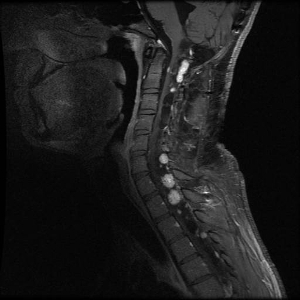

More than 55% of individuals with von Hippel-Lindau disease (VHL) only develop multiple renal cell cysts. VHL-associated renal cell carcinomas (RCCs) are characteristically multifocal and bilateral. These RCCs present as masses with both cystic and solid characteristics.[1] In VHL, the cumulative risk of RCC was reported to be 24% to 45%. RCCs smaller than 3 cm tend to be low-grade (Fuhrman nuclear grade 2) and minimally invasive.[2] However, their growth rate varies widely.[3] An investigation of 228 renal lesions in 28 patients who were followed for at least 1 year showed that transition from a simple cyst to a solid lesion was infrequent.[1] Complex cystic and solid lesions contained neoplastic tissue that was uniformly enlarged. These data may be used to predict the progression of renal lesions (from benign to malignant) in patients with VHL. Figure 1 depicts bilateral renal tumors in a patient with VHL.

Axial view of an individual's midsection showing tumors in both kidneys. The left kidney has a tumor with a dark cystic component and the right kidney has a predominantly solid tumor.

Figure 1. von Hippel-Lindau disease–associated renal cell cancers are characteristically multifocal and bilateral and present as combined cystic and solid masses. The red arrow shows a lesion with a solid and cystic component, and the white arrow shows a predominantly solid lesion.